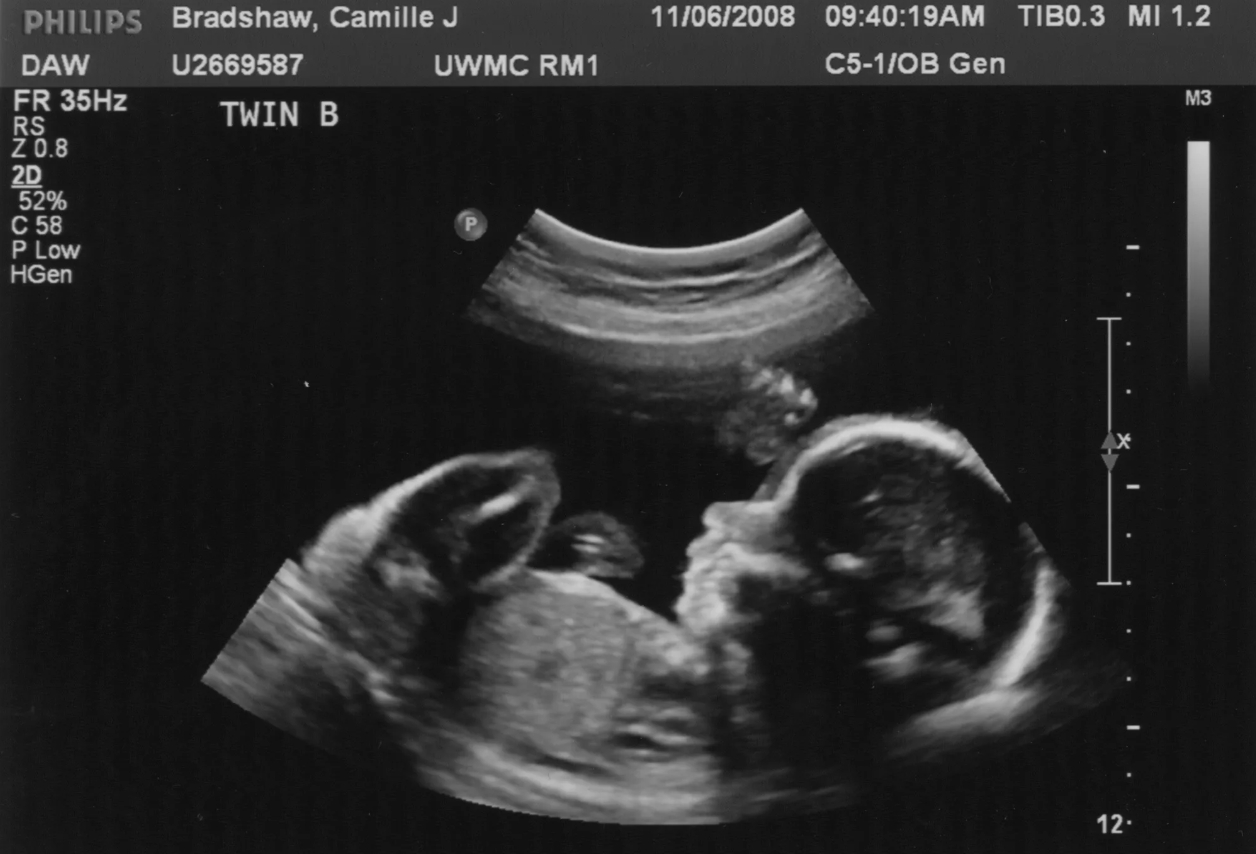

На деле — не особо. Врачи на осмотрах измеряют живот, проверяют положение ребенка, делают УЗИ, но все эти методы дают лишь приблизительное представление. Часто будущих мам пугают «слишком крупным плодом», а на деле ребенок рождается обычного размера. Даже современные исследования показывают, что более чем в половине случаев прогнозы УЗИ о «гигантском малыше» оказываются ошибочными.

Иногда УЗИ ошибаются с размером ребенка. Источник изображения: dishcuss.com